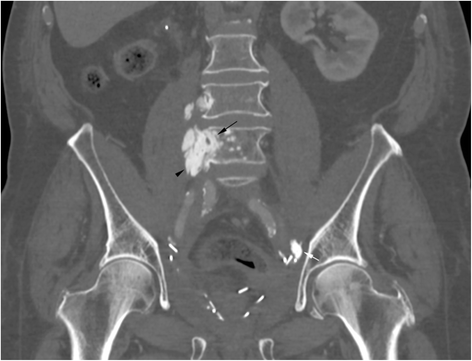

Case presentation: A 75 year-old patient was treated for a high grade transitional cell carcinoma of the bladder by surgery, chemotherapy and radiotherapy. Histology showed foci of bone metaplasia, both at the periphery of the tumor, and in a lymph node metastasis. 1 year later, a heterotopic bone formation was discovered in the right retroperitoneal space, near the lumbar spine, increasing rapidly in size during follow-up. Several imaging exams were performed (2 CT, 1 MRI, 1 Pet-CT), but in the absence of typical features of sarcoma, diagnosis remained unclear. Histology of a CT-guided percutaneous biopsy showed urothelial carcinoma and mature lamellar bone. Integration of these findings with the radiological description of extraosseous localization was consistent with a diagnosis of osseous metaplasia of an urothelial carcinoma metastasis. The absence of bone atypia in both the primary and metastases argues against sarcomatoid urothelial carcinoma with osteosarcomatous differentiation.

Conclusion: Osseous metaplasia of an urothelial carcinoma metastasis is unusual, and difficult to distinguish from radiotherapy induced sarcoma, or from sarcomatoid carcinoma. Rapid progression, sheathing of adjacent structures such as vessels (like inferior vena cava in our case) and nerves and bony feature of lymph node metastases necessitate histological confirmation and rapid treatment. Our case illustrates this disease and evaluates the imaging features. In addition we discuss the differential diagnosis of osseous retroperitoneal masses.